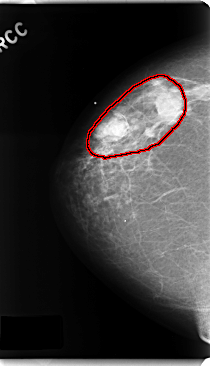

C_0182_1.RIGHT_MLO

RIGHT_MLO LINES 4728 PIXELS_PER_LINE 2696 BITS_PER_PIXEL 12 RESOLUTION 50 OVERLAY

FILE: C_0182_1.RIGHT_MLO.OVERLAY

TOTAL_ABNORMALITIES 1

ABNORMALITY 1

LESION_TYPE MASS SHAPE LOBULATED MARGINS CIRCUMSCRIBED

ASSESSMENT 5

SUBTLETY 5

PATHOLOGY MALIGNANT

TOTAL_OUTLINES 1

BOUNDARY